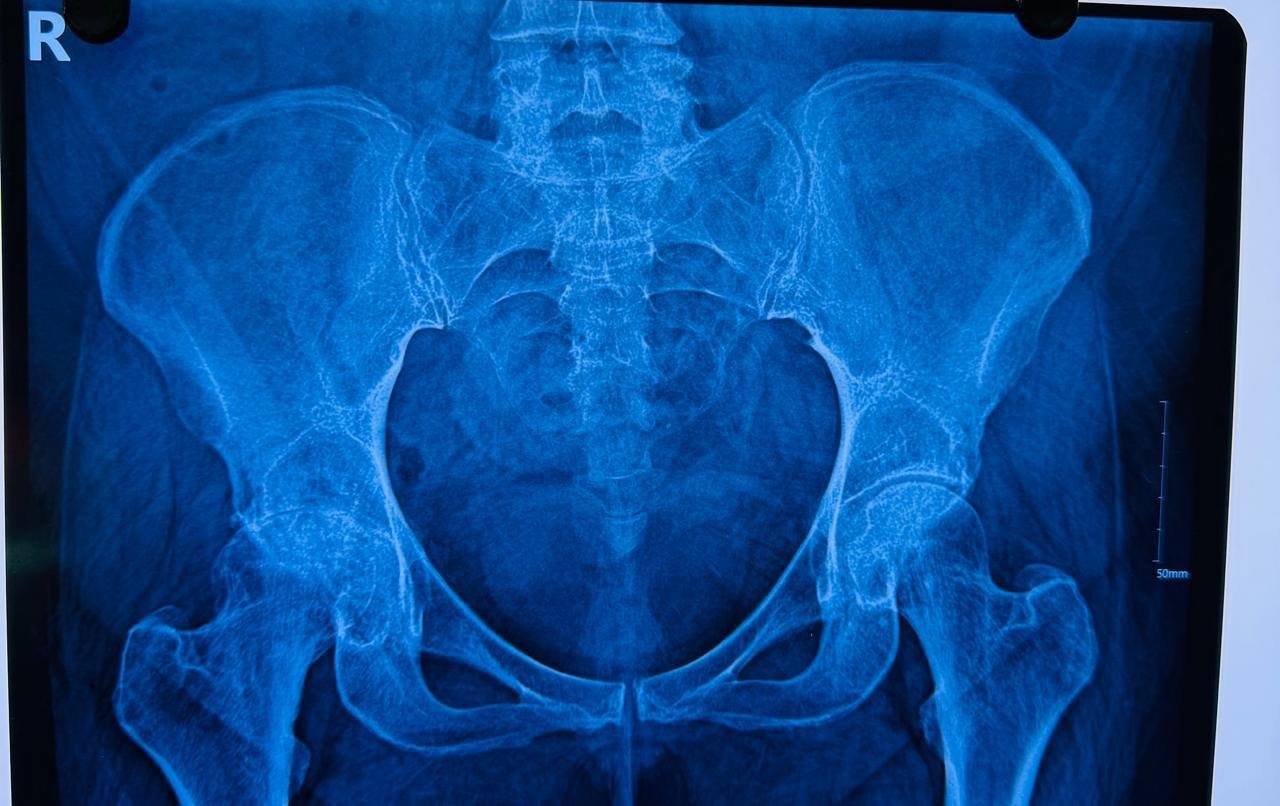

Digital X-Ray Pelvis with Both Hip Joint: True Size AP View

Digital X-Ray Hip Joint: Lat View

Digital X-Ray: Femur Whole Length with Knee Joint (AP/Lat view)

Digital X-Ray: L-S Spine Lateral View (Standing & Sitting)

CT Scan / MRI of Hip Joint (Reserve indication)

III. Pre-Op Templating :

Pre-Operative estimation of probable implant sizes, Offset & LLD

Anticipating any additional inventory if required

Estimation of Sacral Slope